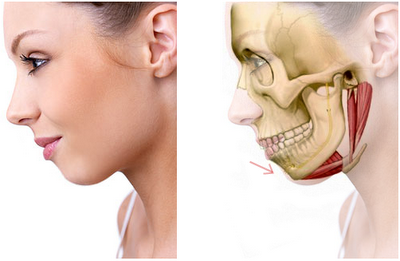

Patología articular

La articulación témporo-mandibular (ATM) es la estructura anatómica encargada de relacionar ambos maxilares. Integrada por el hueso temporal, el cóndilo mandibular y el disco articular, que se interpone entre ambos, guía los movimientos de apertura y cierre bucal, así como los movimientos de lateralidad durante los ciclos de masticación y el habla. Se diferencian en ella dos compartimentos: el superior, entre el hueso temporal y el disco articular, en el que se realiza el movimiento de traslación y un compartimento inferior, entre el disco y el cóndilo mandibular, en el que se realiza el movimiento de rotación. Los diferentes movimientos, así como la limitación de los mismos vendrán determinados por la acción de diversos músculos y ligamentos que participan de la articulación.

Estructura facial y ATM

ATM sana

ATM sana